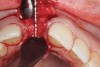

To place an implant without inducing recession, papillae-sparing incisions were created on the mesial and distal of the edentate area at site No. 8. Vertical incisions were made 1 mm away from adjacent teeth and connected with a mid-crestal incision (Figure 13). The extent of the vertical incisions was 3 mm buccally and lingually to expose the alveolar ridge. Horizontal and vertical bone regeneration was clinically confirmed (Figure 14). A 3.3-mm x 12-mm bone level tapered, narrow-connection implant (Straumann, straumann.com) was inserted, and it attained initial primary stability at 25 Ncm (Figure 15 and Figure 16). It was desired to have more than 1 mm of bone buccal and lingual to the implant so as to avoid bone resorption and recession. Then, 4-0 Vicryl single interrupted sutures were used to close the flap (Figure 17).

Fig 13. Papillae-sparing incisions connected mid-crestally.

Figure 13

Fig 14. Clinical confirmation of a 6.4-mm wide ridge.

Figure 14